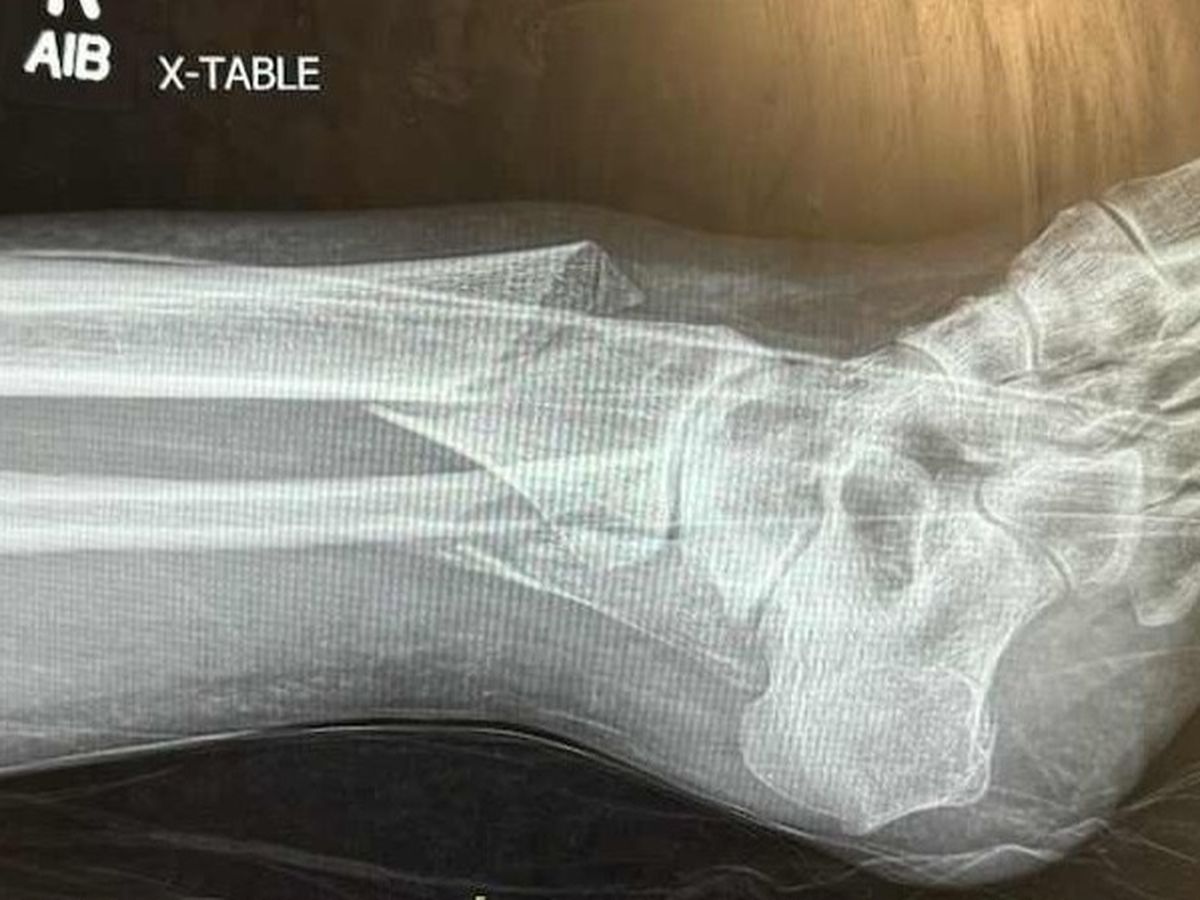

On the evening of Friday, March 15, while out on a first date in downtown Vancouver, my mom slipped in mud while getting into a vehicle, rolled her ankle, and snapped her tibia and fibula.

Instead of calling an ambulance or taking my mom to the closest hospital (St. Paul's), her date thought it would be a good idea to instead take her to the hospital that was on the way home for him (Burnaby Hospital). The longer drive without the assistance of paramedics, resulted in heightened swelling and my mom developing compartment syndrome which is an incredibly painful condition where pressure in the muscles builds to dangerous levels. The severe pain and swelling delayed my mom's surgery by four days. Within that four days, she had to have the bones reset three times and struggled with excruciating pain, unable to move, and was barely able to eat or drink in case she needed to be rushed into surgery.

Luckily, she was able to have her surgery on Tuesday, March 19 where the bones in her leg were secured with plates and rods so they can heal properly. The surgery went well and she is now focusing on healing, managing her pain, and learning to navigate on crutches.